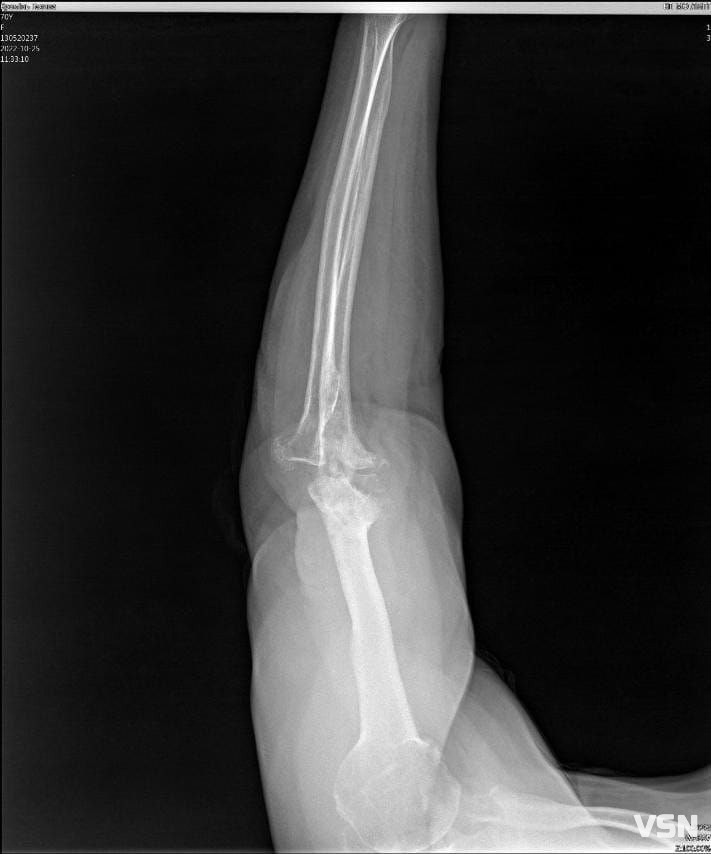

В травні минулого року, поспішаючи на роботу, Галина Кремінь впала та зламала руку, розтрощивши ліктьовий суглоб. Лікарі зробили операцію та вставили пластини, але приєдналась інфекція. Чекаючи зрощення, медики протягом чотирьох місяців рану чистили, обрізали, промивали. Проте, почався остеомієліт. Ще раз прооперували, повиймали пластини та весь метал, почистили кістки. Але суглоб встиг зіпсуватися, і тепер потребує заміни.